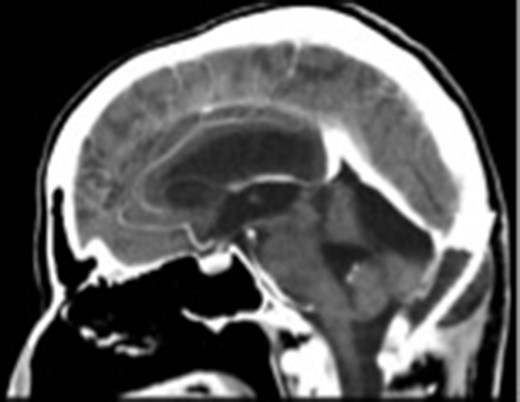

A 55-year-old woman presented with headache, dizziness and gait imbalance for 2 months. Patient’s history revealed a posterior fossa tumor that had been diagnosed 4 years ago prior to admission to our clinic. At that time, contrast enhanced of magnetic resonance imaging (MRI)showed the ill defined lesion, 5.5×3.5×4 cm in size without perilesional edema (Fig. 1A,B). During this 4 years period, her follow-up had been performed with serial MRI (Fig. 2A and B) and CT assessments (Fig. 3). Until 2 months ago, she had only intermittent headache. On neurological examination, she had cerebellar signs including ataxia and also bilateral papilledema through ocular investigations. CT assessment showed punctate calcified lesion demonstrated with undifferentiated margins of the lesion from the cerebellar parenchyma. The last MRI findings showed heterogeneous ill defined lesion without perilesional edema in vermis and extending to the adjoining cerebellar hemisphere at the supracerebellar infratentorial space with a dimension of 6.7×4×4 cm size causing compression of the fourth ventricle and marked hydrocephalous. The patient underwent surgery through a midline supracerebellar infratentorial approach in the prone position. It was a soft whitish intra-axial tumor, moderately vascular with a good plane between the vermis and cerebellum. A complete resection was achieved. The cerebrospinal fluid shunt was not decided to be placed (Fig. 4). Pathological diagnosis was reported as CLN. Immunohistochemical study, synaptophysin and neuron-specific enolase (NSE) immunopositivity were found (Fig. 5). In the mean time, glial fibrillary acidic protein (GFAP) was immunonegative and Ki-67 index was 2%. After operation, she had uneventful postoperative period and was discharged on seventh day.

The postoperative sagittal contrast-enhanced CT scan showing that the tumor had been totally excised.